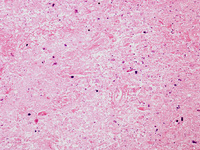

Biópsia do tálamo posterior do paciente com doença de Creutzfeldt-Jakob exibindo as mudanças espongiformes

Do acervo pessoal de Robert E. Schmidt; usado com permissão

Veja esta imagem em contexto nas seguintes seções: